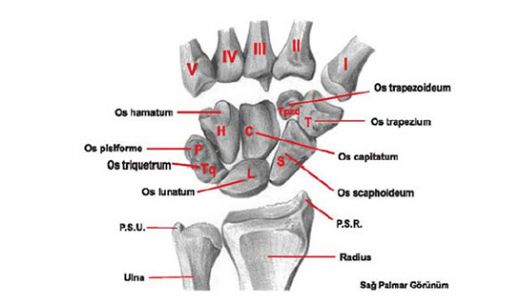

İnsan Kemikleri ve Çeşitler